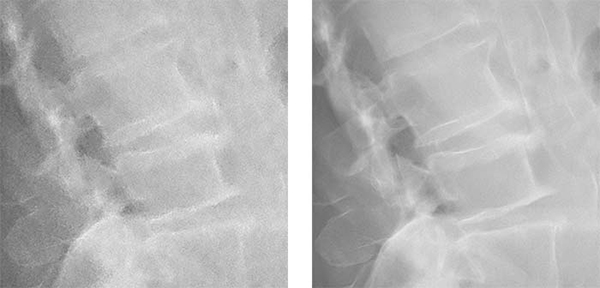

Intelligent NR適用画像イメージ (左:従来処理/右:Intelligent NR適用後)

キヤノンは1998年にDR方式のX線デジタル撮影装置「CXDI」シリーズの販売を開始し,その高い操作性と高画質により顧客の好評を得てきた。今回,AI技術の一つであるディープラーニングを活用することで,これまで以上に粒状感の少ない画像生成を可能にする画像処理技術“Intelligent NR”を開発した。本技術により,医療現場における質の高い診断への貢献を目指すとともに,将来的に少ないX線量での画像生成が可能になることを期待する。

“Intelligent NR”はディープラーニングを活用したキヤノン独自のAI技術で構成され,キヤノンが長年にわたり蓄積してきた「CXDI」シリーズの臨床画像から厳選した約3,000点のX線画像を基に,さまざまな撮影部位におけるノイズの特徴を機械学習している※5。これにより,従来のノイズ低減処理と比較し,必要な画像信号を維持しながら不要なノイズを効率的に除去することが可能になり,最大50%※4のノイズ低減を実現している。